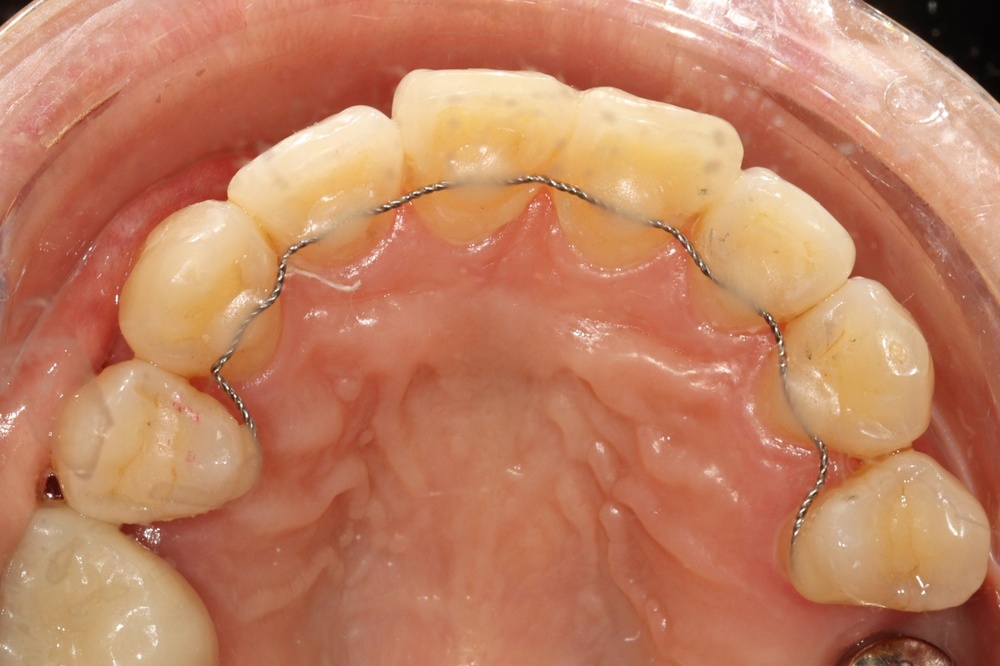

타 치과에서 임플란트 치료중이신 분인데, 교정유지장치 철사(픽스드 리테이너)가 탈락되어서 오셨습니다.

임플란트 진행중인 치과는 교정을 하지 않아서 교정치과로 별도 내원 권유받으셨습니다.

전체 재제작을 위해 기존 유지장치를 제거한 상태입니다.

앞니 잇몸쪽의 벌어짐(블랙 트라이앵글)도 신경쓰인다고 하셔서, 유지장치를 제거하고 레진으로 수복해드리기로 하였습니다.

벌어진 부분을 레진으로 수복하여 틈이 없어졌습니다.

뒤에 교정 유지 철사가 붙어있는 경우 해당치아의 충치치료나 레진빌드업을 위해서는 철사 제거가 필요한 경우가 많습니다.

새로운 교정유지장치 철사도 부착해 드렸습니다.